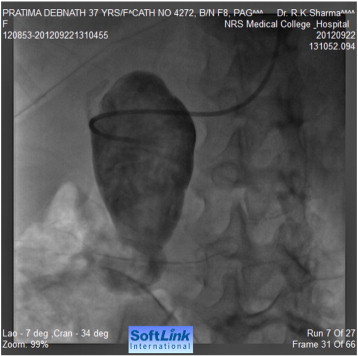

Tran-femoral catheter passage beyond the bifurcation of the abdominal aorta was not possible due to total occlusion and trans-radial aortic angiography showed a long segment of total occlusion (coarctation of abdominal aorta) just below the origin of both renal arteries, multiple dilated collaterals connecting both upper and lower aortic segments with a huge aneurysm involving gastroduodenal artery (Fig. 2, Fig. 3 ;  Fig. 4). Lower thoracic aorta was calcified and arch vessels origins and proximal aorta were normal. The blood pressure within the aneurysm was 190/110 mmHg (Fig. 5).

Selective angiography of feeding vessel to aneurysm via a right Judlins ...

Fig. 4.

Selective angiography of feeding vessel to aneurysm via a right Judlins catheter.

Selective injection into the aneurysm.

Fig. 5.